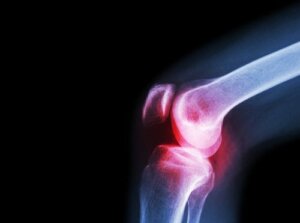

Then, doctors may also conduct an X-ray of the affected joint. X-rays and other diagnostic imaging tools can help evaluate the damage.

The symptoms of septic arthritis vary according to the type of infection. Bacterial infections tend to affect just one joint – typically the knee or hip. In these cases, any movement of the affected joint is very painful. This pain, as well as other symptoms including fever and the chills, tends to develop quickly.

- Redness and inflammation